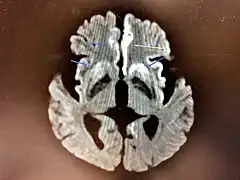

The symptoms of CJD are caused by the progressive death of the brain's nerve cells, which are associated with the build-up of abnormal prion proteins forming in the brain. When brain tissue from a person with CJD is examined under a microscope, many tiny holes can be seen where the nerve cells have died. Parts of the brain may resemble a sponge where the prions were infecting the areas of the brain.[17]

The classic histologic appearance is spongiform change in the gray matter: the presence of many round vacuoles from one to 50 micrometers in the neuropil, in all six cortical layers in the cerebral cortex or with diffuse involvement of the cerebellar molecular layer.[54] These vacuoles appear glassy or eosinophilic and may coalesce. Neuronal loss and gliosis are also seen.[55] Plaques of amyloid-like material can be seen in the neocortex in some cases of CJD.[56]

However, extra-neuronal vacuolization can also be seen in other disease states. Diffuse cortical vacuolization occurs in Alzheimer's disease, and superficial cortical vacuolization occurs in ischemia and frontotemporal dementia. These vacuoles appear clear and punched-out. Larger vacuoles encircling neurons, vessels, and glia are a possible processing artifact.[53]